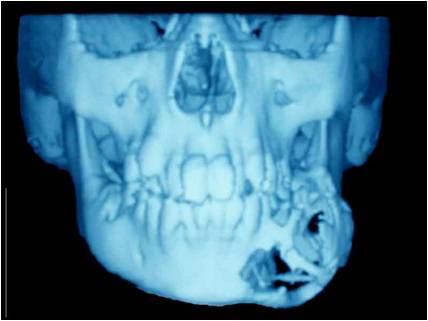

Дете с тумор на долната челюст. Лечението налага нейната резекция. Възстановена е едномоментно чрез микросъдова реконструкция с част от тазова кост. Първата успешна микросъдова долночелюстна реконструкция в България – случай на доц. Джоров.

Пациент със злокачествен тумор на долната челюст наложил резекцията й. Челюстта е възстановена в последствие с помощта на дистракционна остеогенеза – случай на доц. Джоров.

Пациент с доброкачествен тумор, наложил резекция на долната челюст, при която веднага започва възстановяването й чрез дистракционна остеогенза – случай на доц. Джоров.